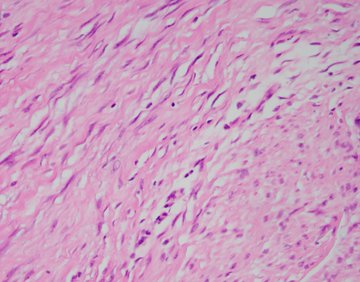

A 34-year-old male presents to the emergency department with abdominal pain. Imaging shows a circumfrential mass causing obstruction of the small bowel. Sections of the mass (H&E shown below) show a mesenteric based spindle cell proliferation with long sweeping fascicles, small blood vessels, bland cytology, no mitoses or necrosis. Immunohistochemical stain for beta catenin shows nuclear positivity in the lesional cells (IHC shown below), and they are negative for desmin, S100, CD117, and SOX10.

Grossly, the lesions are firm with tan-white cut surfaces, often located in the mesentery of small bowel or colon. Histologic sections usually show a low-grade spindle cell proliferation in long sweeping fascicles. Small blood vessels often show perivascular edema. Desmoid fibromatosis should be included in the differential for a spindle cell lesion in the gastrointestinal tract. Other differential diagnoses includes gastrointestinal stromal tumor (GIST), leiomyoma, inflammatory myofibroblastic tumor (IMT), schwannoma, or nodular fasciitis.

Immunohistochemical stains can help differentiate between these. Nuclear staining with beta-catenin is the most helpful stain to confirm desmoid fibromatoses. The other differential diagnoses may show cytoplasmic staining but not nuclear staining. Desmoid fibromatosis may show smooth muscle actin or focal desmin positivity, like leiomyoma, however leiomyoma will not show nuclear beta-catenin staining. Desmoid fibromatosis should be negative for C-kit and DOG1 (positive in GIST), S100 (positive in schwannoma) and ALK (positive in IMT).